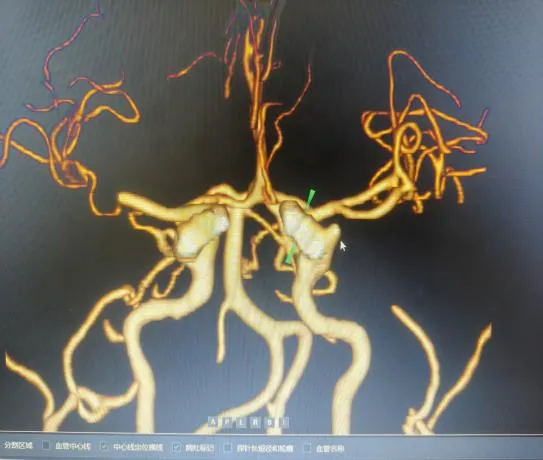

“时间就是大脑,每延迟一分钟,就有190万个神经细胞不可逆坏死!”面对紧急病情,医护团队争分夺秒。快速完成头颅CT等检查后,明确患者符合静脉溶栓指征且无绝对禁忌证,与家属协商签署溶栓同意书后,于22:04立即对患者进行阿替普酶溶栓治疗,DNT时间仅34分钟。然而,溶栓后复查影像学显示,患者大脑中动脉主干仍大血管闭塞,单纯溶栓未彻底开通血管,病情高危。关键时刻,救治团队当机立断,决定采用当前急性大血管闭塞性脑卒中的前沿救治方案——“溶栓桥接取栓”,为患者打通生命通道。

手术室内,神经内科张奕主任凭借丰富经验和精湛技术,在数字减影血管造影机引导下,经毫米级微创通道,将取栓器械精准送达闭塞血管核心部位。经不到1小时操作,成功完整取出堵塞血管的栓子,闭塞血管再通,脑部血供恢复。术后复查头颅 CT显示低灌注区脑组织全部存活。